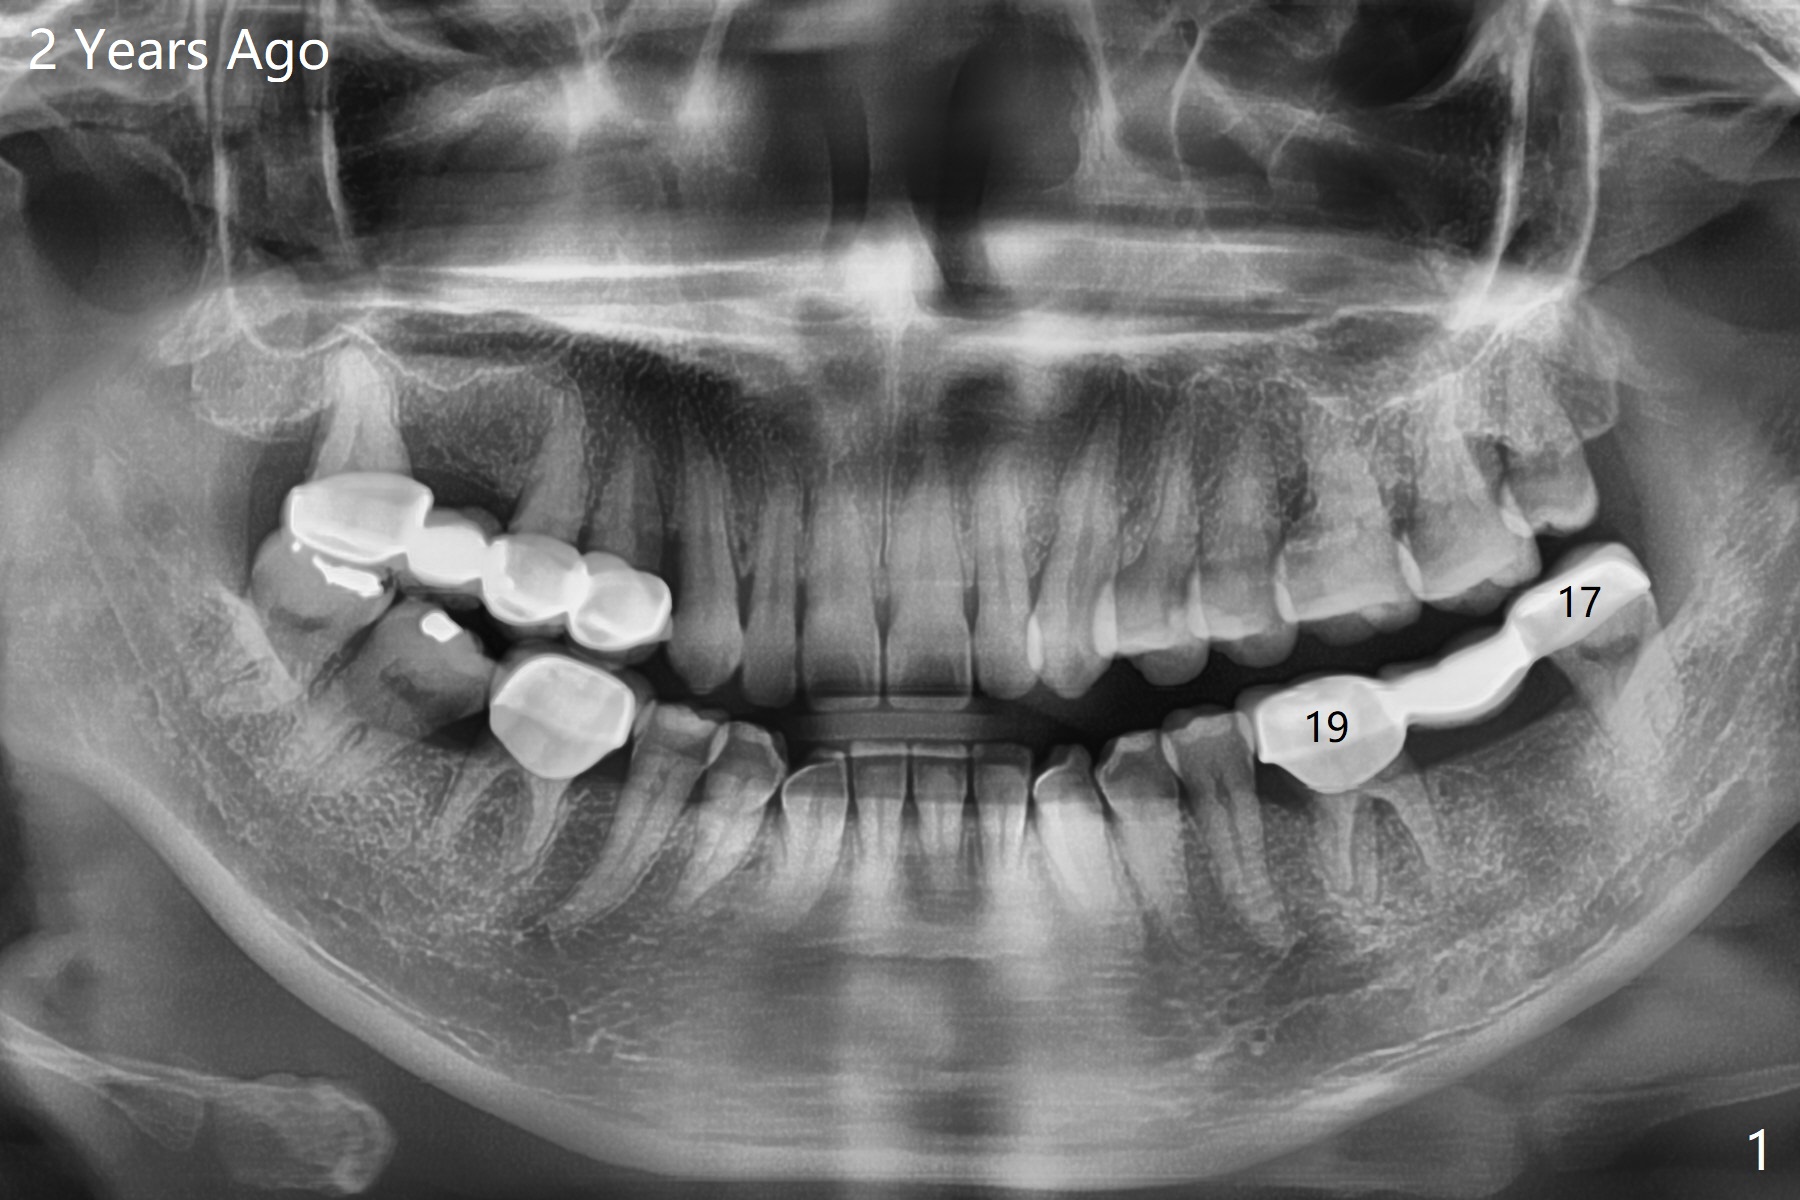

A 35-year-old woman has had guide

Return to No Caries Placement

Xin Wei, DDS, PhD, MS 1st edition 04/15/2021, last revision 05/14/2021